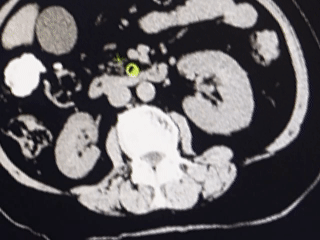

由于既往做过两次开腹手术,尤其是腹腔包虫手术,李奶奶的腹腔内环境被医生预判为“雷区”。在术前评估中,外科团队普遍认为:腹腔粘连的可能性极大。通常情况下,面对这样的腹部手术史,医生往往会选择传统的开腹手术,以确保安全。但这也意味着,老人将要承受又一次长达10多厘米的切口创伤,对于高龄且合并糖尿病的她来说,伤口愈合慢、感染风险高,术后恢复将是一场漫长的考验。

当腹腔镜探查镜头探入腹腔的那一刻,情况果然如术前所料:腹腔内广泛粘连,腹腔内形成了致密的“蜘蛛网”,所幸胆囊没有包裹其中,解剖层次相对清晰,这为微创操作的继续进行提供了宝贵的机会。